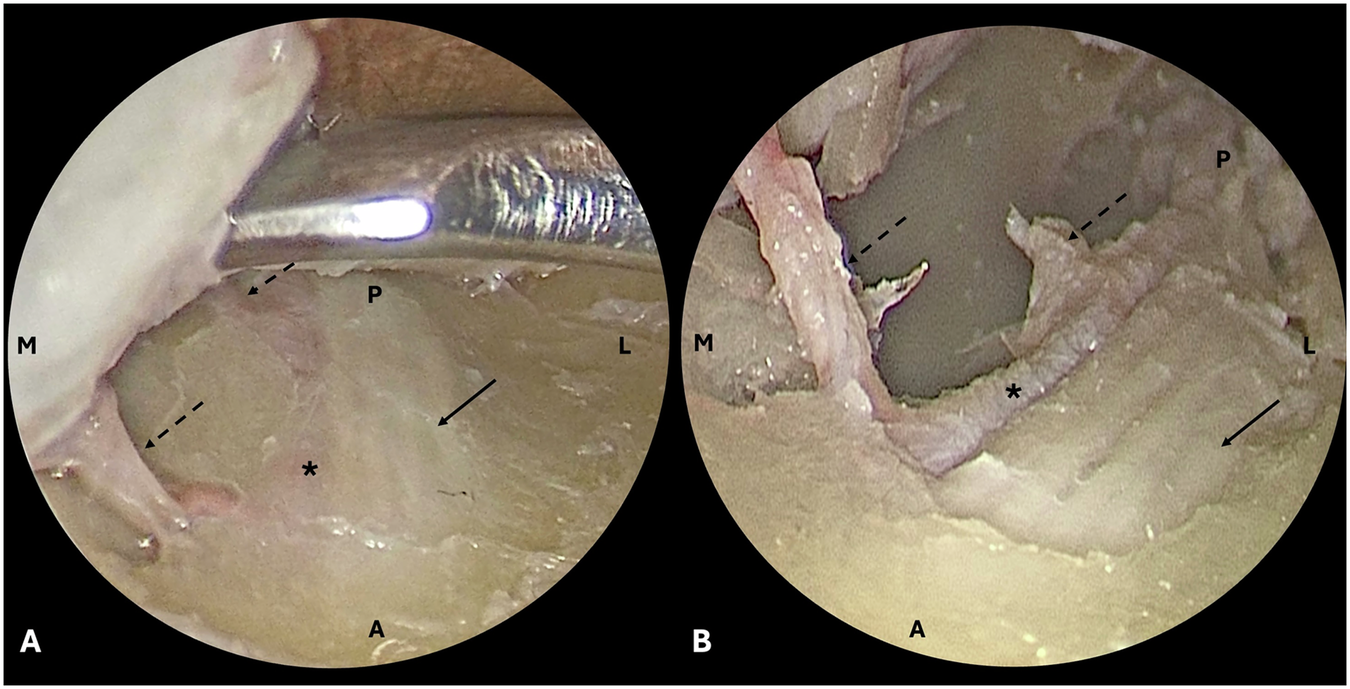

Fig. 1: Cadaveric dissection demonstrating two orbital branches of the infraorbital artery.

The infraorbital nerve (ION, solid arrow), infraorbital artery (IOA, asterisk) and orbital branches of the IOA (dashed arrows) are demonstrated. A anterior, L lateral, M medial, P posterior. A Orbital floor dissection in the subperiosteal plane demonstrates the ION within its canal, with the IOA running medially. B Once the roof of the infraorbital canal was removed, the IOA and its two orbital branches could be clearly identified travelling medial to the ION.